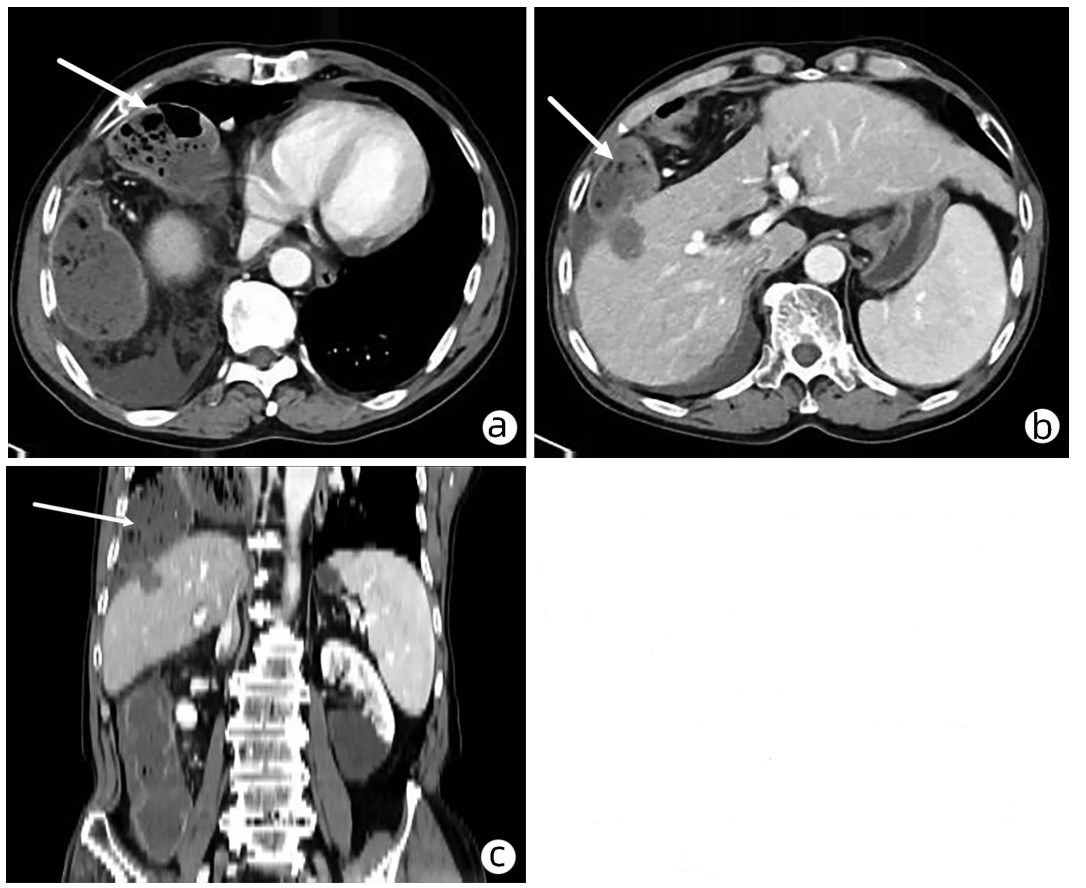

肝细胞癌微波消融术后迟发性膈疝1例报告

王晓栋, 张玉蓉, 朱晓宁, 郑丁, 汪静

2022, 38(8): 1875-1877. DOI: 10.3969/j.issn.1001-5256.2022.08.029

摘要(875) HTML (328) PDF (2572KB)(61)

摘要: